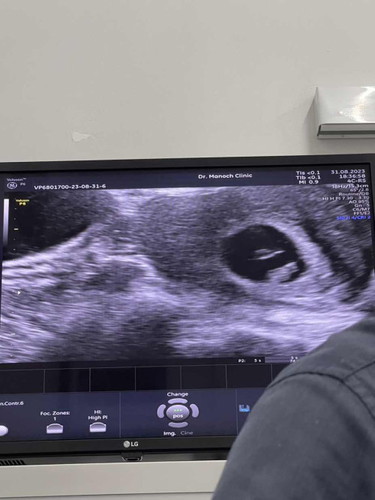

ตอนนี้ได้ 7 สัปดาห์แล้ว เจอตัวน้องแล้ว แต่ก้อนกลมๆ ตรงกลางถุง คืออะไรคะ

ถุงไข่แดงค่ะ มีไว้ให้น้องรับสารอาหาร จะสลายไปเองตอน 4-5 เดือนค่ะ